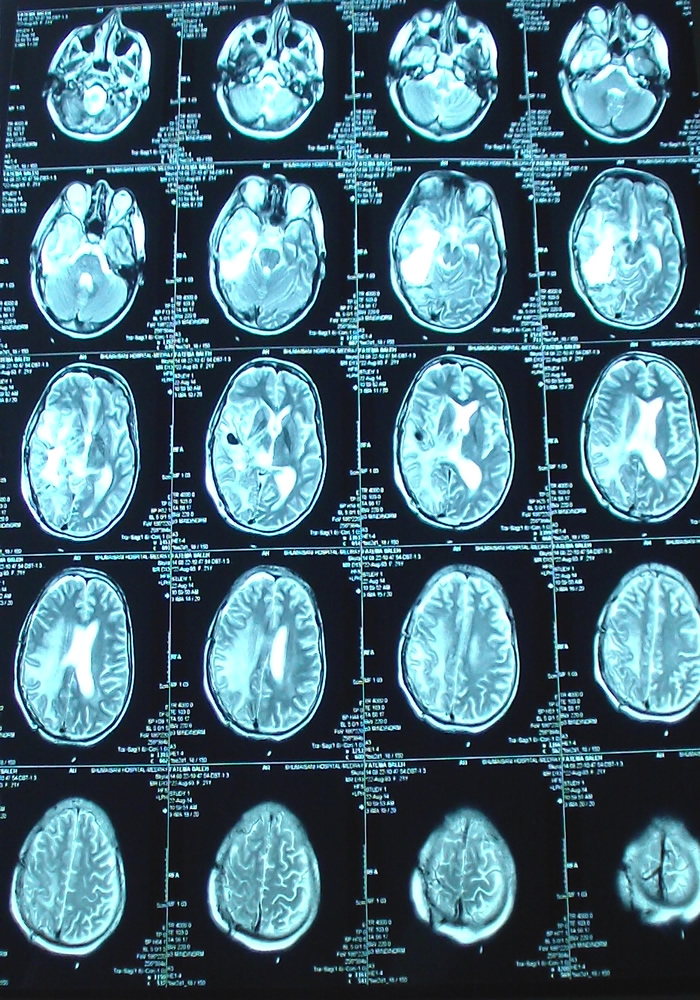

21-AUGUST-2014  FATMEH SALEH AL-DROOBI  20 YEARS RECURRENCE OF HIGHLY MALIGNANT GLIOMA RIGHT CONVEXITY.

Axial TW2 done the second postoperative day.